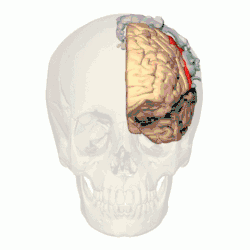

Research studies using functional magnetic resonance imaging (or fMRI) have found the increased activity of certain brain parts when one experiences the sensation of tickle. An increased cerebral blood flow in the somatosensory cortex - or S1 - is shown in response to tickle induced by an external stimulus (McGlone et al., 2002). This particular area of the cortex is the primary receiver of sensory inputs from the body relayed via the thalamus (Hine & Martin, 2015). The S1 occupies the postcentral gyrus and is devoted to process information from the somatic receptors (Colman, 2008). When one receives an externally administered tactile stimulus that produces the tickle sensation, the S1 shows an increased activity, suggesting that tickle is indeed a fundamental sensation of the skin.

One of the unique characteristics of tickling is that one cannot make oneself laugh via self-tickling. The sensation of tickle is perceived by a part of the brain called the somatosensory cortex, or S1. However, when tickle is felt as a sensation resulting from a self-produced stimulation, the S1 does not show the same increase in activity as it does during an externally administered stimulation (Blakemore, Wolpert, & Firth, 1998). This suggests that a self-produced tactile stimulus is perceived by the brain as less ticklish than the same stimulus generated externally. It is important to note, however, that most research on the subject relies heavily on self-report, and subjective experiences of the sensation of tickle vary among individuals (Simpson, 2001). Thus, further research using a different method is required to reduce the current strong degree of subjectivity.

The neural root of ticklish laughter in humans has been found to be within the limbic system. A study using an fMRI revealed a significant role of hypothalamic activity in evoking ticklish laughter (Wattendorf et al., 2013). It was found that tickling followed by involuntary laughter activated parts within the limbic system, which are the lateral hypothalamus and amygdala, as well as the parietal operculum and the right side of the cerebellum (Wattendorf et al., 2013). Tickling was also found to activate the higher-order sensory regions which has been associated with the conscious perception of both skin contact and pain (Watterndorf et al., 2013), which may explain the defensive reaction people engage in when being tickled.